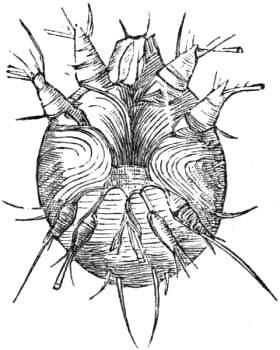

| 223. | THE ITCH MITE, | 689 |